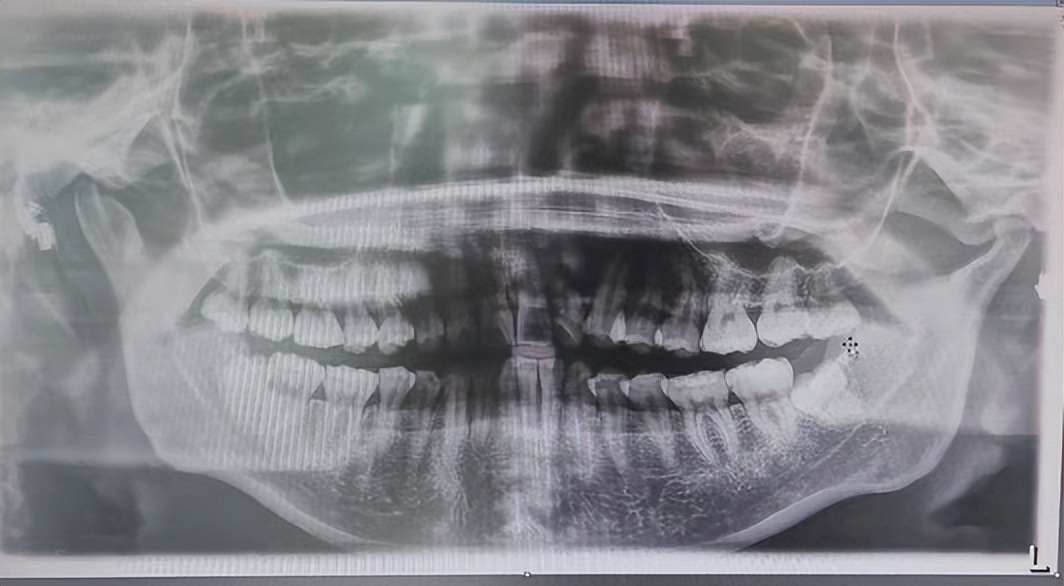

媳妇疼痛部位是下智齿,但是她两颗下智齿均未生长出来,只能先拍牙齿影像图一探究竟。

结果发现两颗下智齿全部顶着侧面的臼齿在生长,这也是牙齿疼痛的原因,如果不及时治疗,智齿会将臼齿顶坏,到时后果将更加严重。

媳妇的畸形智齿